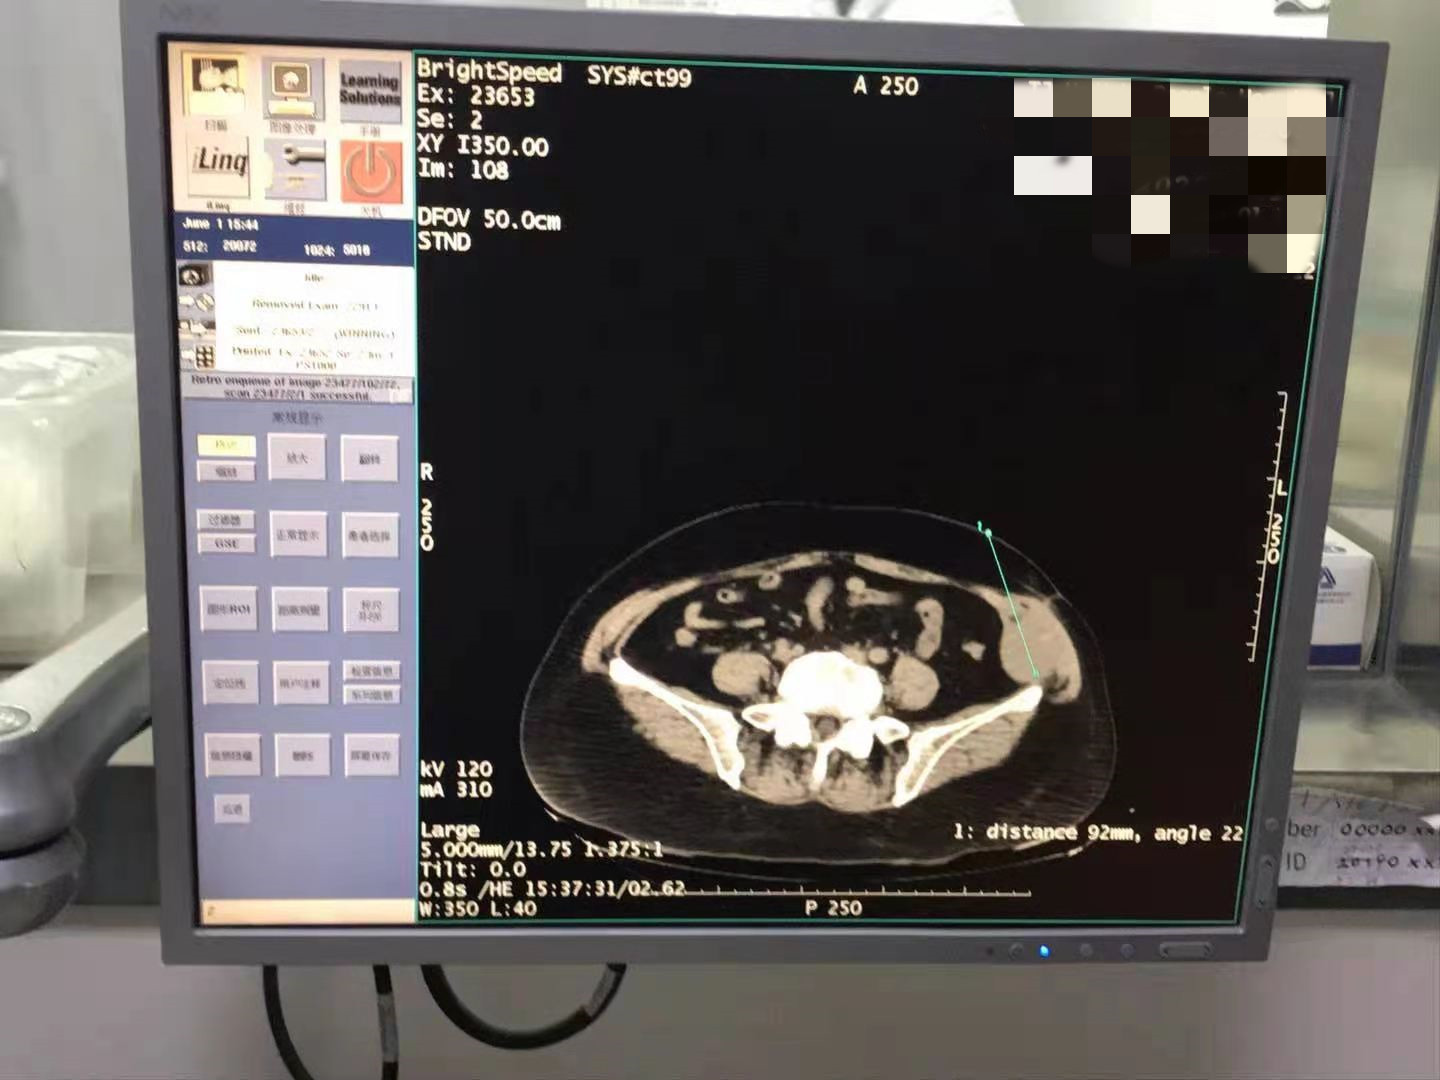

2021年6月份腹部肉瘤氩氦刀手术

发布人:美国氩氦刀技术官方网站    发布时间:2021/9/22 15:50:29